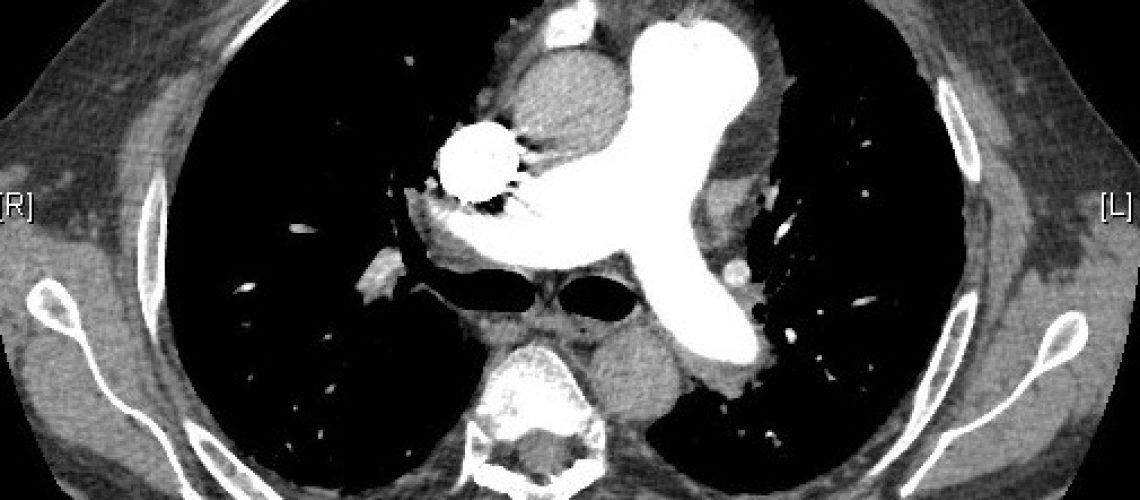

La Hipertensión Arterial Pulmonar es una enfermedad grave que afecta a  la arterias pulmonares.  Suele aparecer entre la 3ª y 4ª década de la vida y es más frecuente en mujeres. En el 6% de los casos existen antecedentes familiares de la enfermedad que se transmite siguiendo un patrón de herencia autosómico dominante con penetrancia reducida. Los síntomas mas comunes son la dificultad para respirar, la fatiga y el dolor torácico y algunos pacientes pueden presentar sincopes, mareos o palpitaciones. El diagnóstico se basa en la ecocardiografía y se confirma con el cateterismo del corazón derecho. El tratamiento se realiza con fármacos vasodilatadores que disminuyen la presión en las arterias pulmonares, reservándose el trasplante pulmonar para aquellos pacientes que no responden al tratamiento médico.